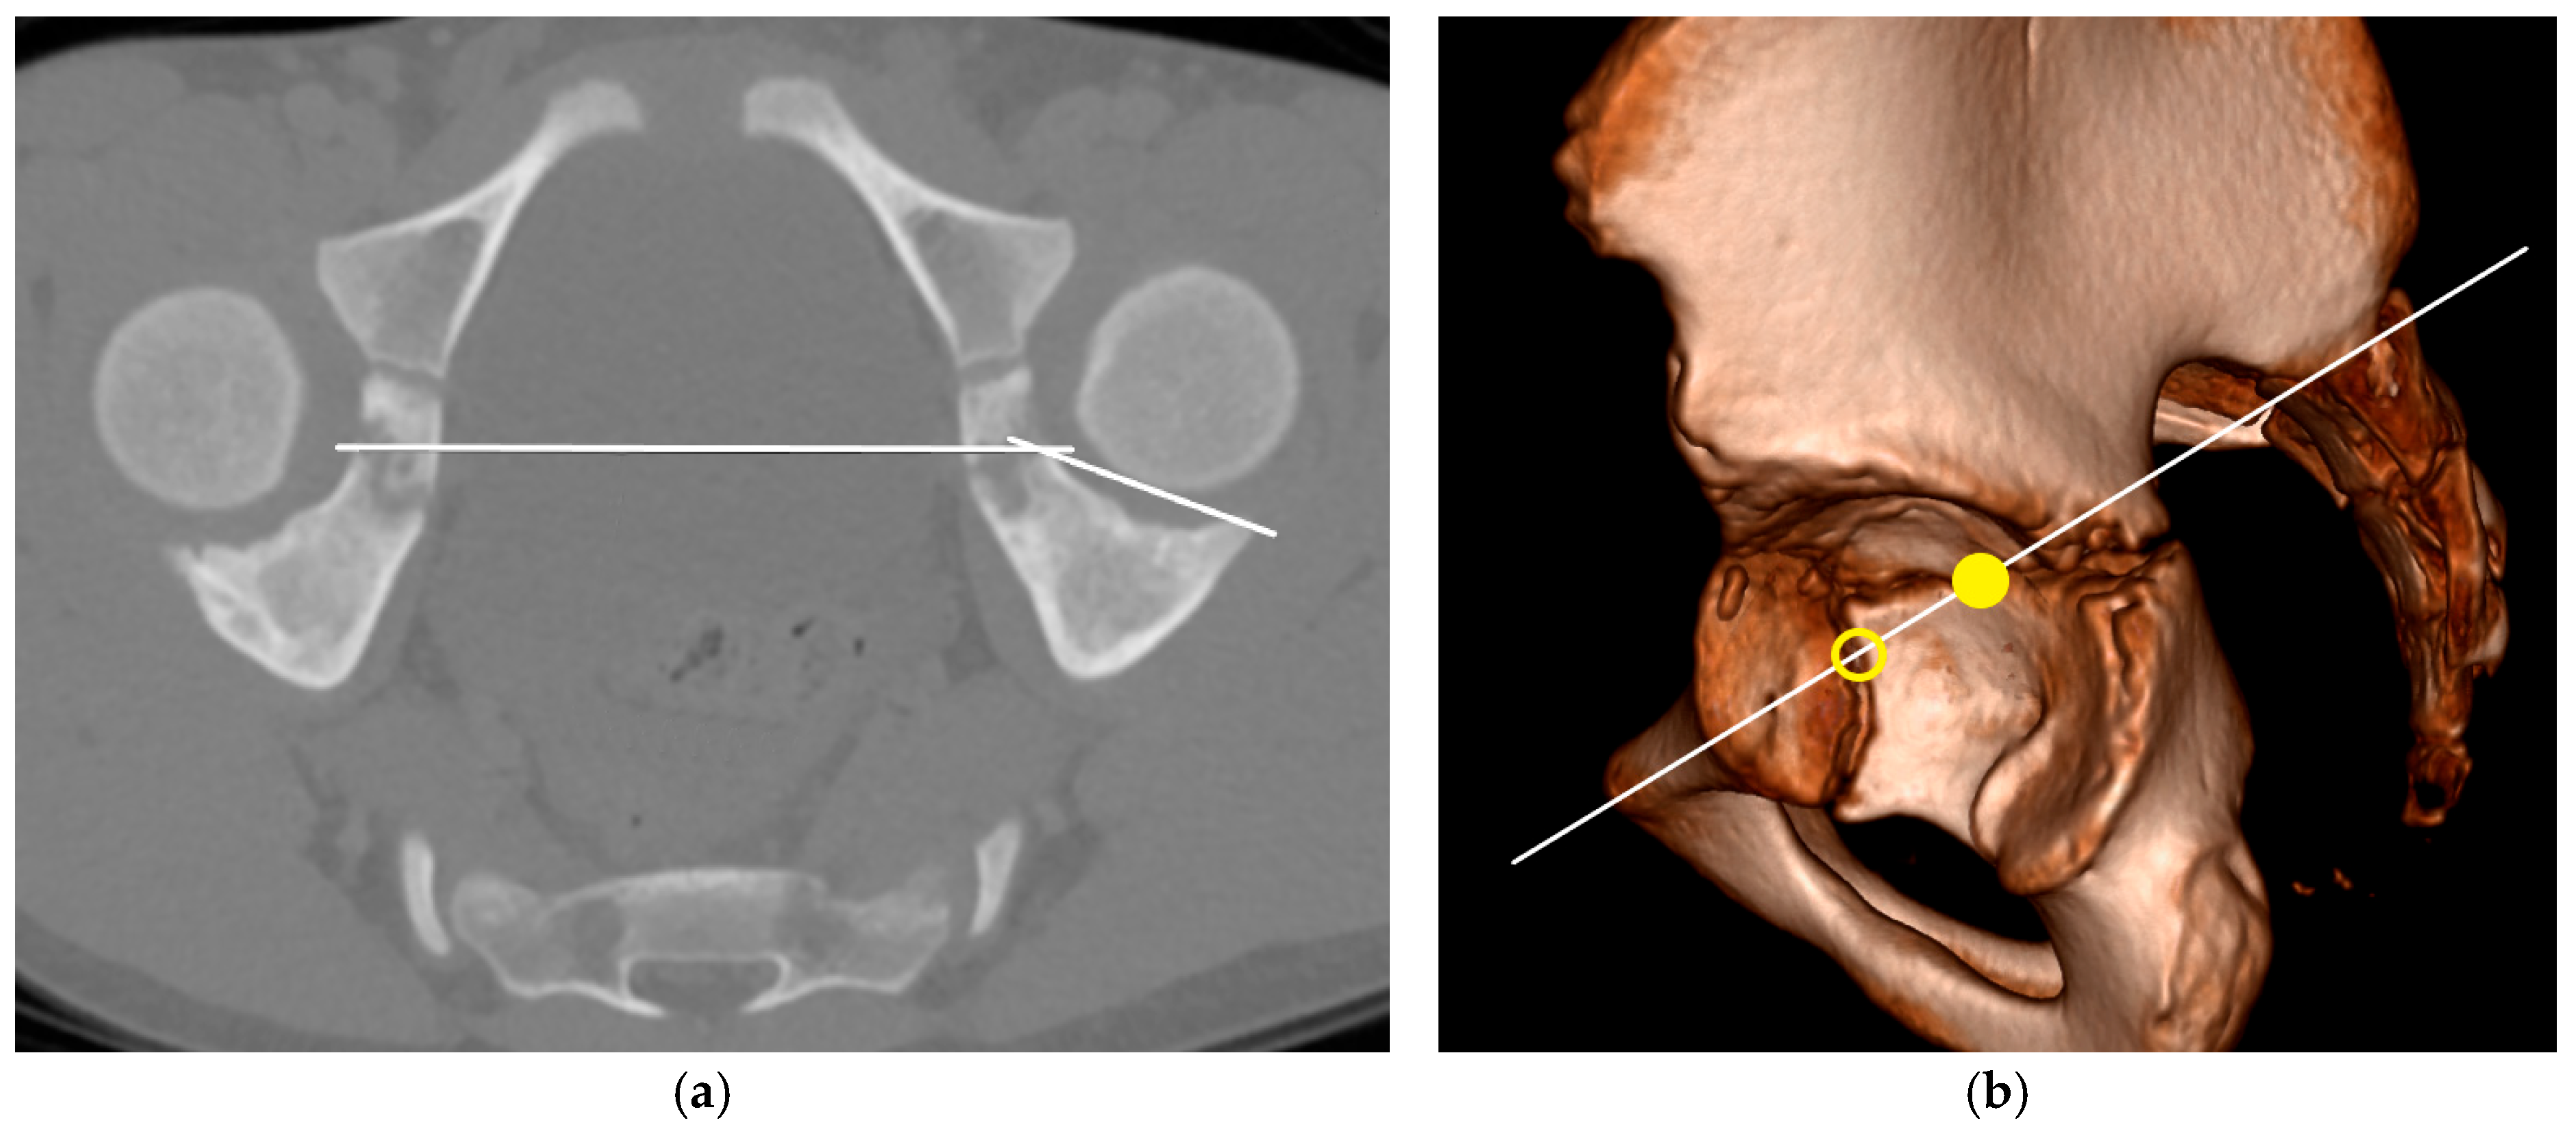

For the objective assessment of acetabular defects in the CT scans, we used the 3DAI method introduced by Chung et al. [15]. This method consists of three measurements: the anterosuperior index (ASI), the superolateral index (SLI) and the posterosuperior index (PSI). To obtain these values, we generated oblique plane images through multiplanar reformation. The measurements were conducted simultaneously with the description by Chung. When forming the plane for the PSI, both the inferior and posterior limbs of the triradiate cartilage are displayed. Contrary to Chung’s description, we decided to use the posterior limb and not the inferior limb as the coordinate for evaluation. In our anatomical understanding, the posterior limb forms the lower boundary of the acetabular roof formed by the ilium (Figure 1).

Figure 1. (a) Reformatted CT scan for the measurement of the PSI, (b) Plane of the PSI with intersection of the triradiate cartilage in the posterior (point) and inferior limb (circle).